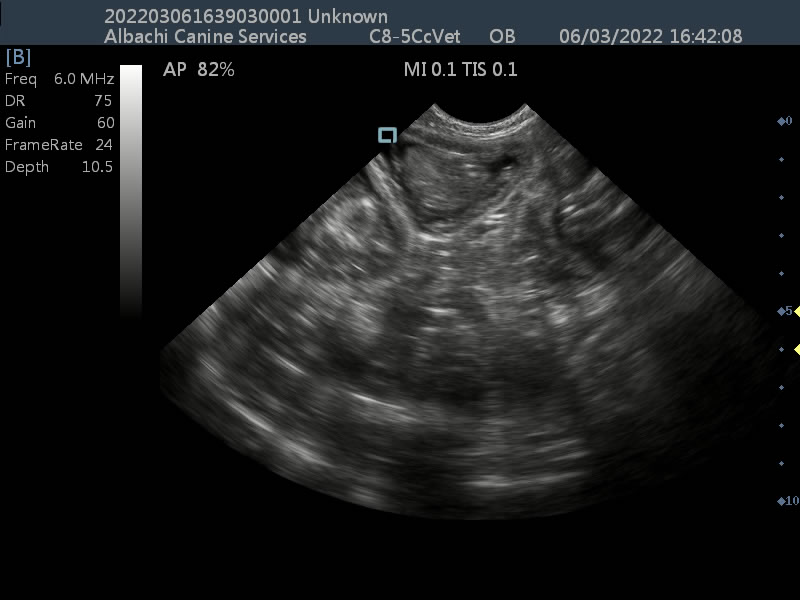

A late stage scan for Elsie the Pomeranian, showing development of pups. Videos and images show developed organs and heart beats.